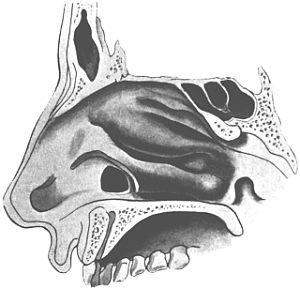

| 310. | Semi-diagrammatic Transverse Section of the Nose | 610 |

| 311. | Operation for Perforation of the Septum | 612 |